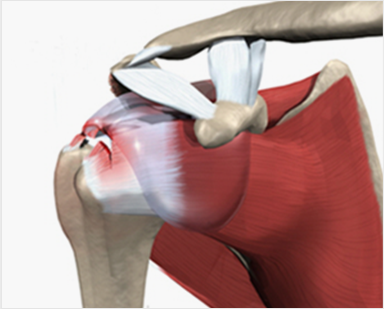

회전근개의 구조

극하근, 극상근, 소원근, 견갑하근 총 4개의 근육으로 구성

회전근개의 파열

근육이 다 끊어지는 경우는 드물며 근육의 일부가 부분적으로 패이거나 늘어지거나 하는 경우가 많다.